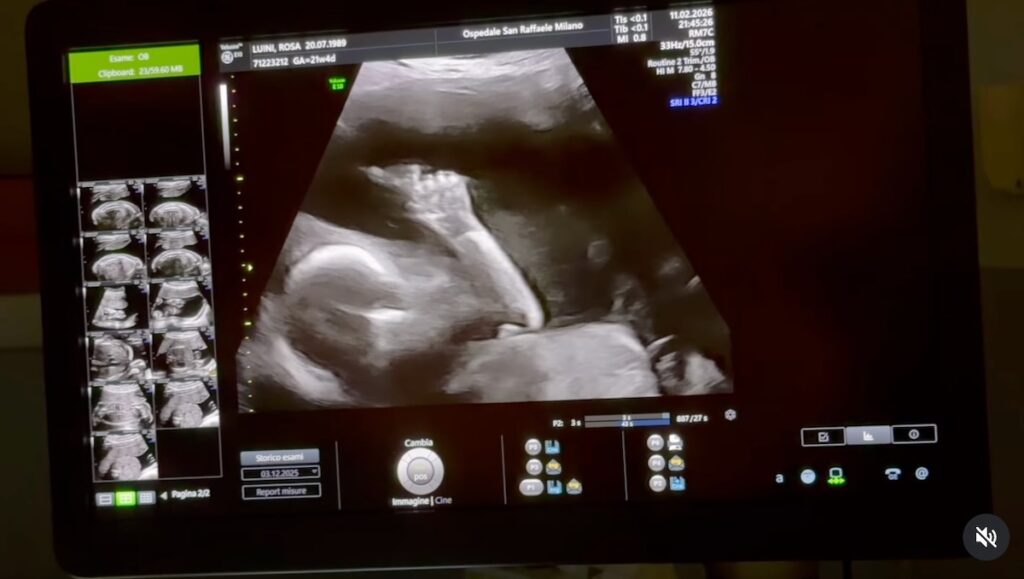

La protagonista della notizia è Rose Villain, all’anagrafe Rosa Luini, che ha rivelato di essere incinta del suo primo figlio. La cantante celebre anche per i suoi capelli celesti ha deciso di comunicare la gravidanza in un modo molto speciale: pubblicando su Instagram, nella giornata dell’11 marzo, il video del suo nuovo brano intitolato Tuttaluce. Non si tratta soltanto di una nuova uscita musicale, ma di un racconto intimo della sua gravidanza.

Nel videoclip e nel testo della canzone l’artista ripercorre infatti alcuni momenti significativi della scoperta di essere in dolce attesa. Le immagini mostrano il percorso che va dalla sorpresa iniziale fino alla condivisione della notizia con la famiglia, passando per i primi mesi vissuti accanto al marito. Nel brano emergono parole molto intense, dedicate proprio al bambino che nascerà.